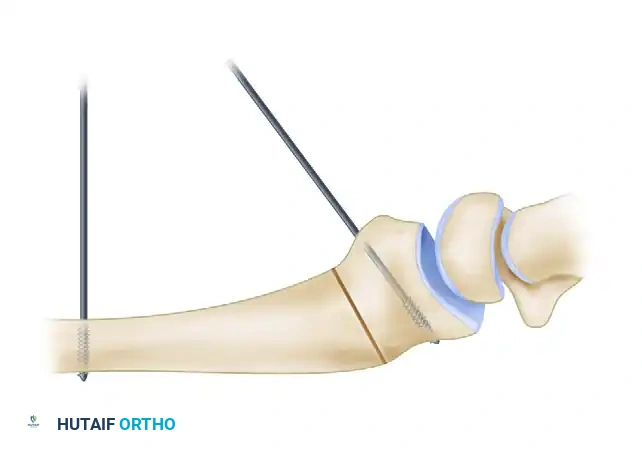

2. Placement of Reference Kirschner Wires

Before creating the osteotomy, establish a mechanical reference for the planned correction.

* Drill a smooth 0.062-inch or 0.045-inch Kirschner wire (K-wire) into the radial diaphysis, proximal to the planned osteotomy site, strictly perpendicular to the long axis of the radius.

* Drill a second 0.062-inch K-wire into the distal articular fragment at the predetermined angle of the deformity in the sagittal plane.

🔪 Surgical Warning

The placement of these reference wires is critical. Once the osteotomy is completed and the distal fragment is mobilized, these wires will be manipulated until they are parallel, visually confirming that the exact degree of planned sagittal correction has been achieved.